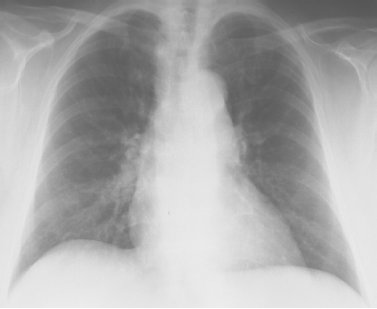

17. Struktur a auf dem Röntgenbild ist (siehe Abbildung 4 [Abb. 4])

□ Die Aorta (f)

□ Die Luftröhre (r)

□ Die Speiseröhre (f)

□ Die Wirbelsäule (f)

□ Weiß ich nicht